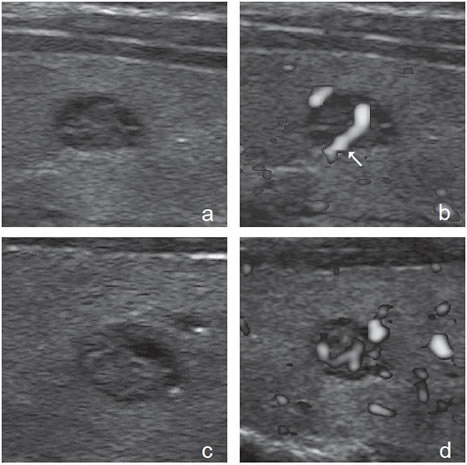

Patrones semejantes de distinta etiología

En un 15 a 20% de los casos la apariencia de los nódulos benignos y malignos es muy parecida, y prácticamente imposible de diferenciar, de manera que es inevitable recurrir a la PAAF (Figura 44). Muy excepcionalmente un nódulo con un patrón clásico de benignidad resultará ser un cáncer papilar (Figura 45a, b, c y d). En estos casos la única clave puede ser la presencia de adenopatías, motivo por el cual la exploración del cuello debe ser completa.

Figura 45. a) y b) Cáncer papilar que simula un

nódulo coloideo de apariencia benigna, que al

“doppler color” muestra un vaso penetrante (flecha);

c) y d) Nódulo coloideo de similares características

al de la figuras 45 a) y 45 b), que también

muestra vascularización central Por último, existe una variedad de cáncer papilar esclerosante, que no se presenta como un nódulo, sino como un aumento de tamaño difuso de la glándula, con una estructura gruesa, heterogénea, hipoecogénica con abundantes microcalcificaciones difusas (Figura 46a y b). Es frecuente el compromiso metastático de los linfonodos cervicales y ocurre en pacientes jóvenes24.